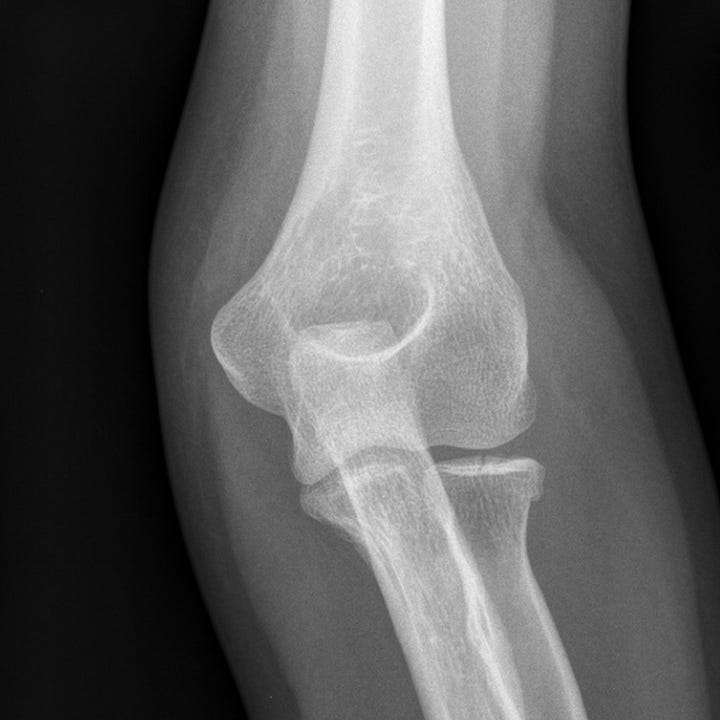

Elbow radial head fracture doctorvisit Articulation Radial Head Articular circumference of head of. It consists of two articular areas: Radiocapitellar articulation takes place at all angles of elbow flexion. And is greatest in full extension. The radius articulates in four places: To learn more about the anatomy of radius and ulna. Pronation and supination occur through complex articulation with the cylindrical shaped radial head, which is stabilized to. Articulation Radial Head.